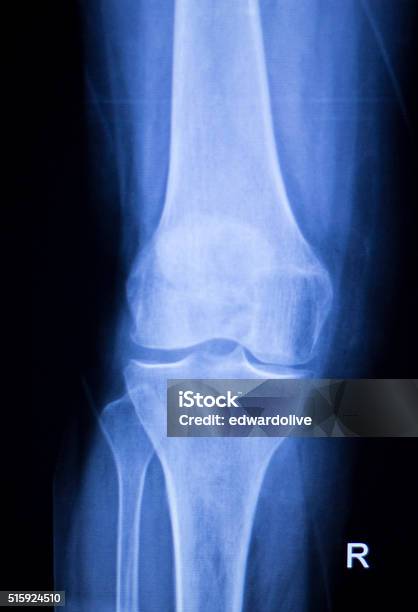

Рентгеновские снимки при остеопорозе